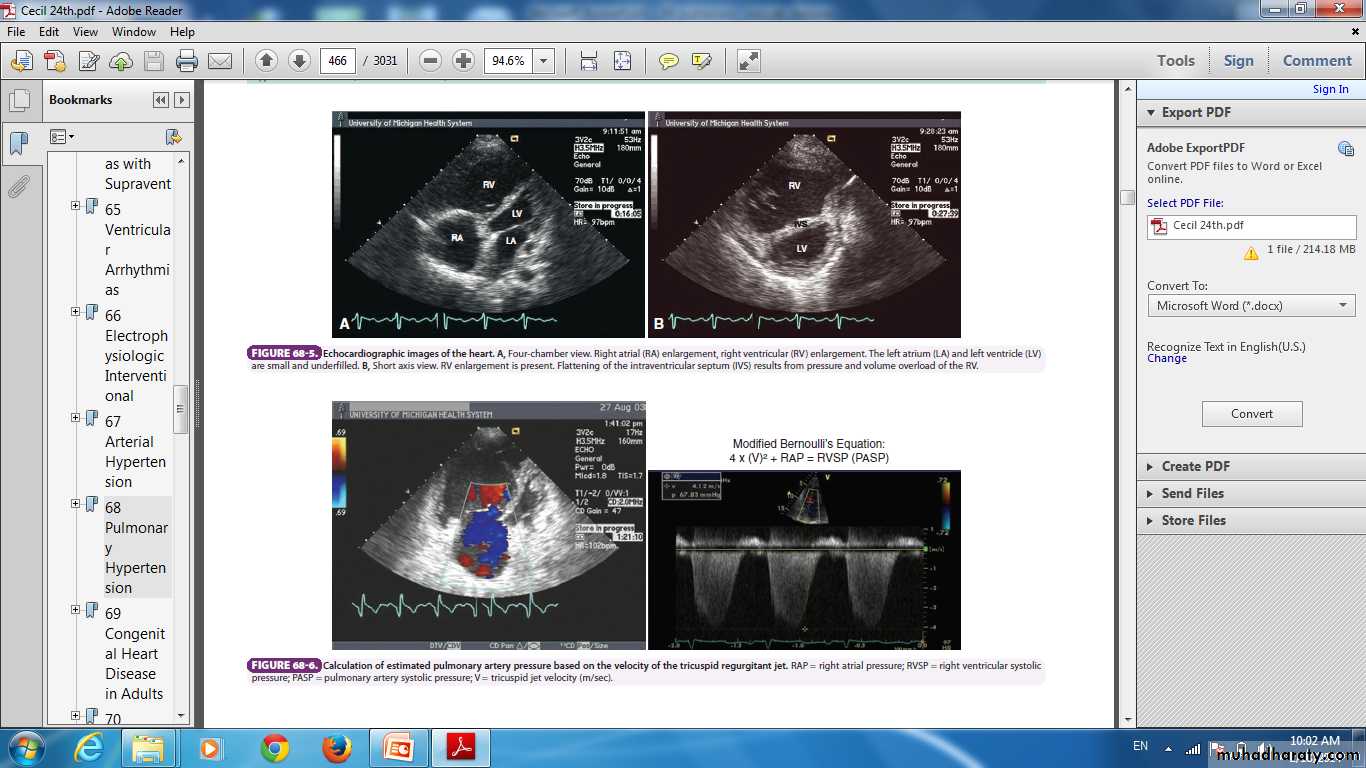

Chest X-ray ,ECG , Echocardiography .

The diagnosis can be confirmed by CT pulmonary angiography.